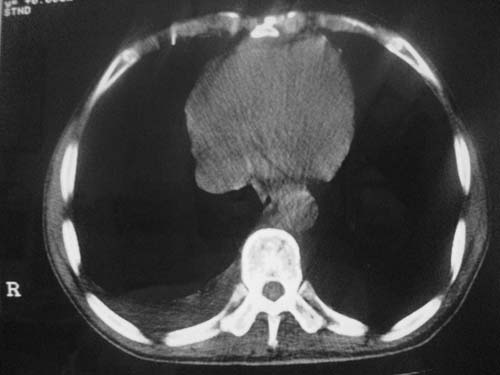

以下是引用科室第一人在2010-3-25 20:30:00的发言:[br]1:纵膈肿瘤性病变,恶性胸腺瘤可能性大伴纵膈右肺门淋巴结转移,右侧胸腔积液。[br]2:右侧肺门肿瘤性病变,纵膈淋巴结转移,右侧胸腔积液。右下叶转移。

以下是引用子期在2010-3-25 21:00:00的发言:[br]先考虑右中央型肺癌伴转移。

以下是引用江广1996在2010-3-25 22:49:00的发言:[br]通常肺癌向纵隔转移多见,纵隔肿瘤向肺内转移少见(有的表现为向肺内侵润)。本例以一元论考虑:右中心型肺癌并纵隔淋巴等多处转移。[br][br][本贴已被 江广1996 于 2010-3-25 22:50:07 修改过]

以下是引用yangyudong333在2010-3-26 6:43:00的发言:[br]“冰冻纵膈”,考虑纵膈淋巴瘤伴肺内及胸膜侵润。